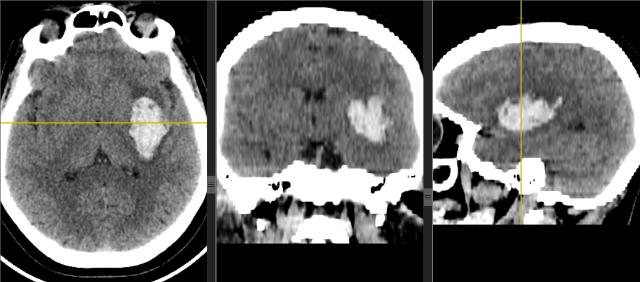

Инсульт удаление гематомы

Инсульт удаление гематомы 108 фотографий